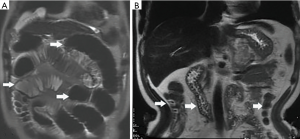

Among the AP patients, wall thickening involved duodenum (Figure 1) (27%), ascending colon (26%), stomach (20%), transverse colon (15%), jejunum (Figure 2) (14%) and ileum (6%). Dilatation of the gastrointestinal tract was seen in 8% (Figure 2, Table 2).

In this study gastrointestinal tract wall thickening was the most common finding in AP patients. Inflammatory substances can stimulate the gastrointestinal tract in patients with AP, leading to the excessive output of gastric juices and subsequent mucosal and submucosal edema (27). Some patients exhibit a three-layer structure referred to as the “target sign” (28). Tolan et al. (29) considered this pattern acute wall edema, and noted a direct correlation with inflammatory activity. In this study we found most AP patients exhibited gastrointestinal tract wall thickening, some with a stratified appearance on MRI that was similar to the “target sign” (28). After treatment, the mural stratification resolved on follow-up MRI. Our results suggested that the thickened intestinal wall in AP patients is derived from acute wall edema and can resolve soon after treatment.

We found frequent mild smooth thickening of the intestinal wall, similar to that of other non-tumorous bowel wall thickening patterns. Ramalho et al. (30) observed that the wall thickness usually ranges between 5 and 10 mm for patients with small bowel Crohn’s disease, similar to the range we noted (Table 2) in AP patients. Bowel wall thickening has been observed in bowl ischemia edema, bleeding and infection, although this thickness was unrelated to disease severity (31). Gastrointestinal tract wall thickness reduced after treatment, suggesting resolved edema after effective treatment.